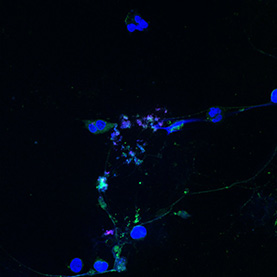

Our bodies have an impressive capacity to heal themselves; unfortunately, the nervous system regenerates much less easily than other vital tissues. Implants of materials that can support or guide the regrowth of cells could help the nervous system recover from injury or disease.

These images reveal the efforts of researchers to coax rat brain cells to grow across a surface of graphene, a material chosen for its toughness, flexibility, and ability to conduct electrical signals. The cells cannot easily implant on the graphene, and in early trials clung to each other instead. In later trials, the addition of the right mix of proteins to the graphene surface enabled cells to implant, grow, and form a healthy, web-like network.

Scientist Collaborator

Hyunjoon Kong Laboratory

Zeiss LSM 700 Confocal Microscope

National Science Foundation